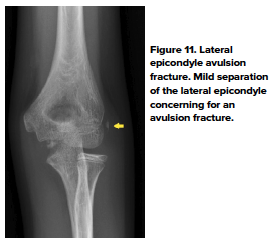

- Lateral epicondylar fracture

- Lateral epicondylar fractures are extremely rare and usually occur between ages 9-15 years. In the older child, these fractures are due to a direct blow to the lateral epicondylar region and are usually associated with other injuries of the elbow.11 In younger children, avulsion forces from the forearm extensor muscles are responsible, likely due to a reaction mechanism.7 Pain and soft tissue swelling of the lateral epicondylar region are common complaints from patients with this fracture (Fig 11).